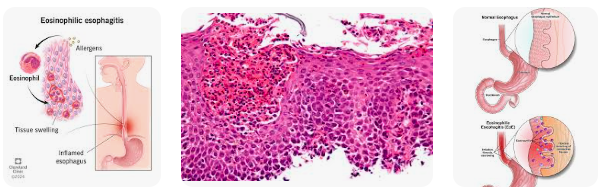

Viêm thực quản tăng bạch cầu ái toan (Eosinophilic esophagitis-EoE)) là một dạng bệnh lý thuộc nhóm bệnh viêm hệ tiêu hóa tăng bạch cầu ái toan (EGID) xảy ra tại vị trí thực quản. Bạch cầu ái toan (BCAT) thâm nhiễm nhiều trong thực quản, gây đỏ, sưng phồng và tổn thương. EoE ngày càng được nhận ra và chẩn đoán nhiều ca bệnh hơn ở thực quản. Tỷ lệ mắc mới tình trạng này gia tăng theo các bệnh lý mạn tính, bệnh rối loạn dung nạp thức ăn như từng xảy ra tại Úc và được chẩn đoán thường bắt đầu do bệnh nhân phàn nàn về khó nuốt hay nuốt vướng.

EoE là một rối loạn dịu ứng ang gia tăng lưu hành ở thực quản. Đặc trưng lâm sàng bởi các rối loạn chức năng thực quản (oesophageal dysfunction) và về mặt vi thể có thể viêm thâm nhiêm BCAT ở thực quản. Điều trị liên quan đến việc tránh các thực phẩm và liệu pháp thuốc corticosteroid cần gián đoạn hay lâu dài do bản chất bệnh hay tái phát. EoE có thể cải thiện thông qua cải thiện chất lượng sống bệnh nhân.

Hình 1. Viêm thực quản tăng bạch cầu ái toan và hình ảnh mô học sau sinh thiết

|Nguồn: Cleveland Clinic, 2024